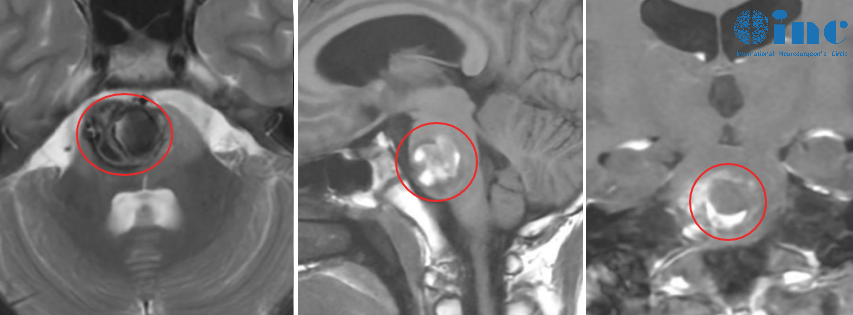

然而,三月后的复查结果一度使全家再度陷入忧虑。MRI报告显示:脑干区域存在异常信号,考虑为海绵状血管瘤可能;同时发现右侧天幕下有一处蛛网膜囊肿。焦虑不已的父母立即联系巴教授,却意外获得教授的乐观回应:无需担忧,这实际上是好消息!

巴教授在远程评估小雨的最新影像后表示:“好消息!患儿临床状态良好,这与MRI结果相符。”又三个月后,得知巴教授即将来华,小雨母亲特意带孩子前往苏州,一方面为当面致谢,另一方面也希望教授亲自评估孩子状况。此次,巴教授给出了更详细的解释:报告中所谓的“异常信号”并非肿瘤残留,而是含铁血黄素沉积,这对于像小雨这样曾罹患巨大出血性脑干病变的患者属于正常现象,并不代表存在活跃的海绵状血管瘤。此外,针对蛛网膜囊肿,巴教授宽慰道:“若无症状,无需任何治疗,不必过分担心。”教授肯定而自信的回答,终于让小雨全家放下心中重石。

需知的是,脑干海绵状血管瘤易出现反复微量出血,当脑组织存在慢性出血或血管损伤时,其代谢产物可导致含铁血黄素沉积。这类沉积并非疾病状态,正如巴教授所言,对于像小雨这样接受巨大海绵状血管瘤全切除的病例,属正常术后表现。